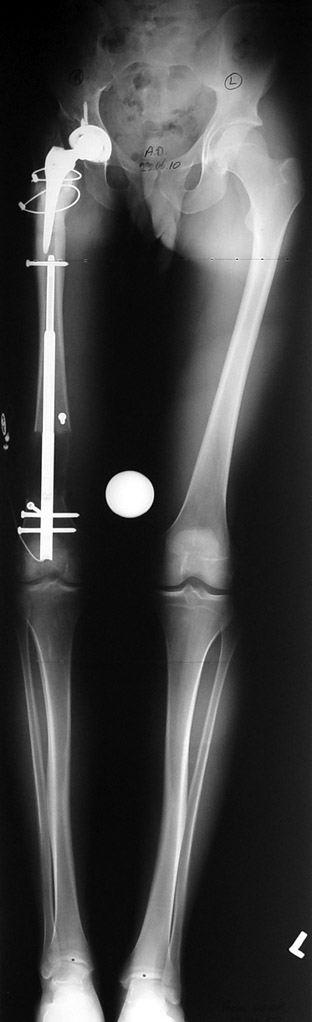

Vaka 1